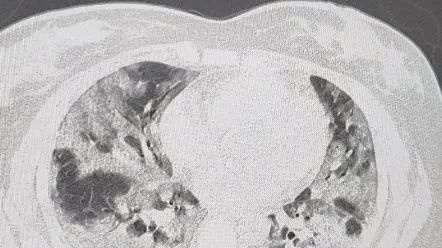

不同于奥密克戎在其它国家的表现,也不同于上海疫情期间多数为无症状感染者的情况,这波中国疫情,不仅绝大多数感染者有明显症状,而且重症率也有明显升高,尤其表现在肺部感染上。

那么,为什么中国“大白肺这么多“呢?美国癌症医生张玉蛟教授在微博等社交媒体平台分享了他的观点,总结了三点: